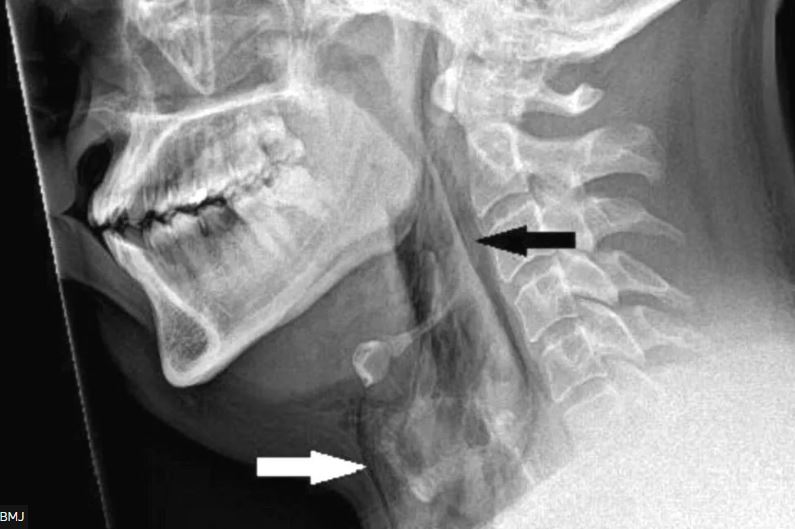

2018-ban szintén az Egyesült Királyságban történt, hogy az orvosoknak egy 34 éves férfit kellett ellátni, akinek elszakadt a légcsöve, miközben megpróbált visszafojtani egy nagy erejű tüsszentést. A férfi azt mondta, hogy a tüsszentés során "pattanó" érzést tapasztalt, ezután pedig azonnal nagy fájdalom hasított a nyakába, ami miatt utána a nyelés és a beszéd is nehezére esett. Amikor az orvosok megvizsgálták, duzzanatot és érzékenységet tapasztaltak a férfi torka és nyaka körül, a röntgenfelvétel pedig kimutatta, hogy a levegő a légcsőből egy repedésen keresztül a nyak lágyszövetébe távozik. A férfit a következő hét napban csövön keresztül kellett táplálni, hogy a szövetek begyógyulhassanak, az egy hetes kórházi kezelés után a beteg teljesen felépült.